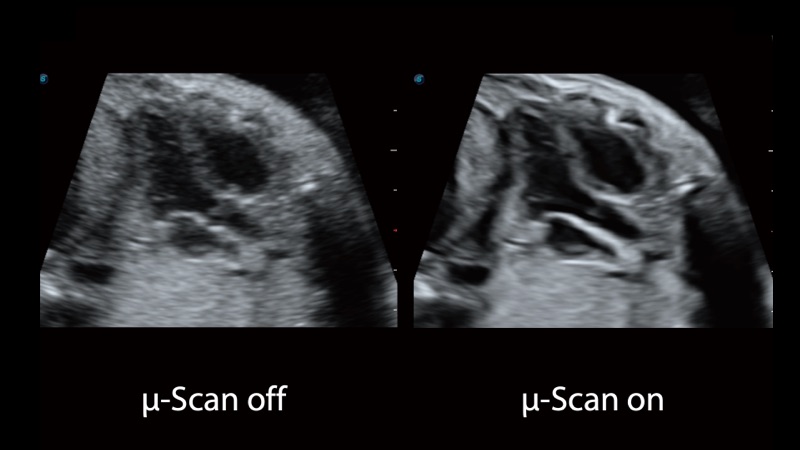

开立医疗通过不断的技术创新,为大众的生命健康提供持续关爱。P12 Plus采用全新一代超声成像平台,新平台旨在将真实还原组织解剖结构作为首要目标。平台采用全新集成化硬件模块,搭载新一代芯片,系统性能得到大幅提升,为您的诊断提供了丰富的临床信息。优异的图像表现,丰富的探头配置,全面的应用功能,为您日常诊断提供了可靠的助手。

凭借开立医疗先进的成像技术和优异的探头技术提供的清晰的图像表现,您可以更自信地做出临床决策。